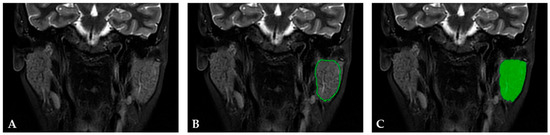

2.3. Texture Analysis Protocol and Statistical Analysis

2.3.1. Image Preprocessing and Segmentation